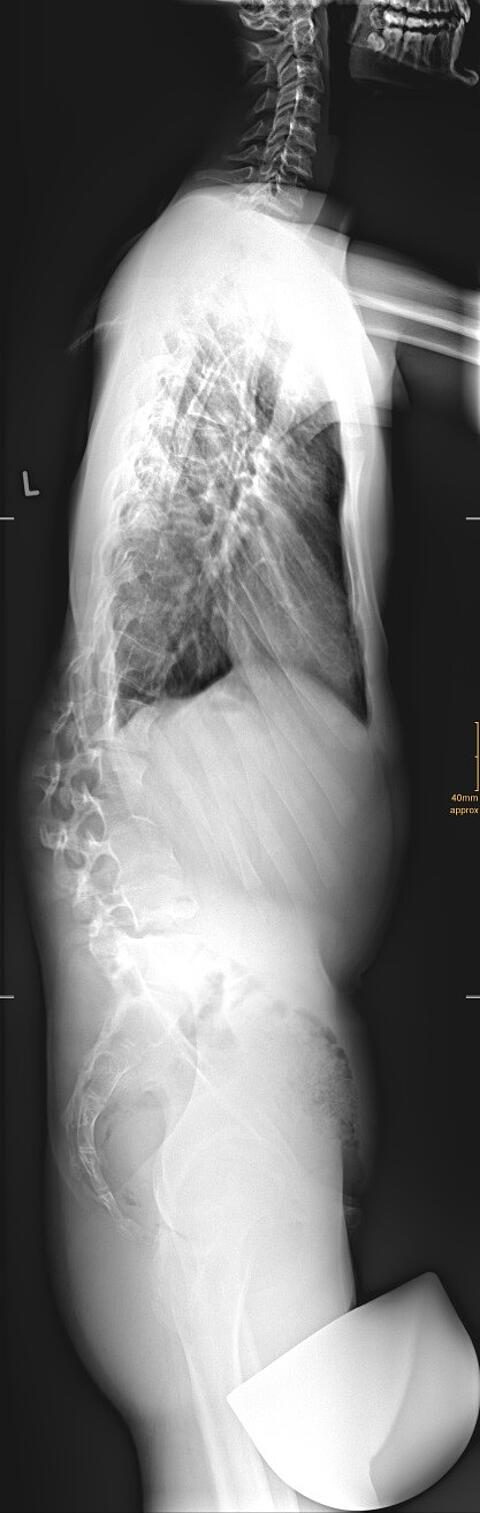

Neben stehend sehen sie eine solche Röntgenaufnahme der gesamten Wirbelsäule und des Beckens. Für eine solche Aufnahme müssen 4 Bilder aufgenommen werden und dann werden diese zusammengesetzt. Hierbei ist eine verzerrungsfreie Aufnahme jeder einzelnen Ebene wichtig. Bei unserem Multitom fährt die Röntgenröhre und der entsprechende Detektor parallel die Etagen ab und es kommt zu einer optimalen und verzerrungsfreien Darstellung. Gleichzeitig ist die verwendete Strahlenexposition extrem niedrig, da die neuesten Röntgentechnologien verwendet werden. In dem Beispiel erkennt man eine massive Verkrümmung der Lendenwirbelsäule nach links.

Neben der seitlichen Verkrümmung kommt es häufig auch zu einer Fehlkrümmung der Wirbelsäule in seitlicher Richtung. Dies bewirkt ein Ungleichgewicht nach vorne oder hinten und die Patienten. Durch die perfekt zusammengesetzte Untersuchung der Wirbelsäule in allen Abschnitten kann diese sog. „sagittale Imbalance“ präzise vermessen werden.